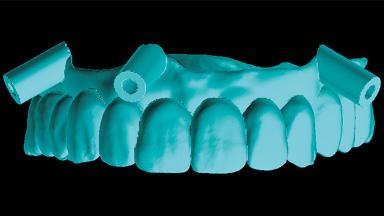

Rehabilitating an Edentulous Maxilla with a Fixed Dental Prosthesis Using a DSD-Guided Approach

A 60-year-old man was referred to the Center of Excellence for Prosthodontics and Implant Dentistry (CEPI) of the School of Dentistry of the University of São Paulo, Brazil for implant therapy. Anamnesis, clinical examination, and radiographs revealed esthetic and functional problems, the absence or structural compromise of various teeth (16–11, 21, 22, 24, 25, 37, 45, and 48), periodontal and endodontic problems (17 and 27), implant fracture (46), and occlusal disorders . The patient reported that he was undergoing treatment for cardiovascular diseases.